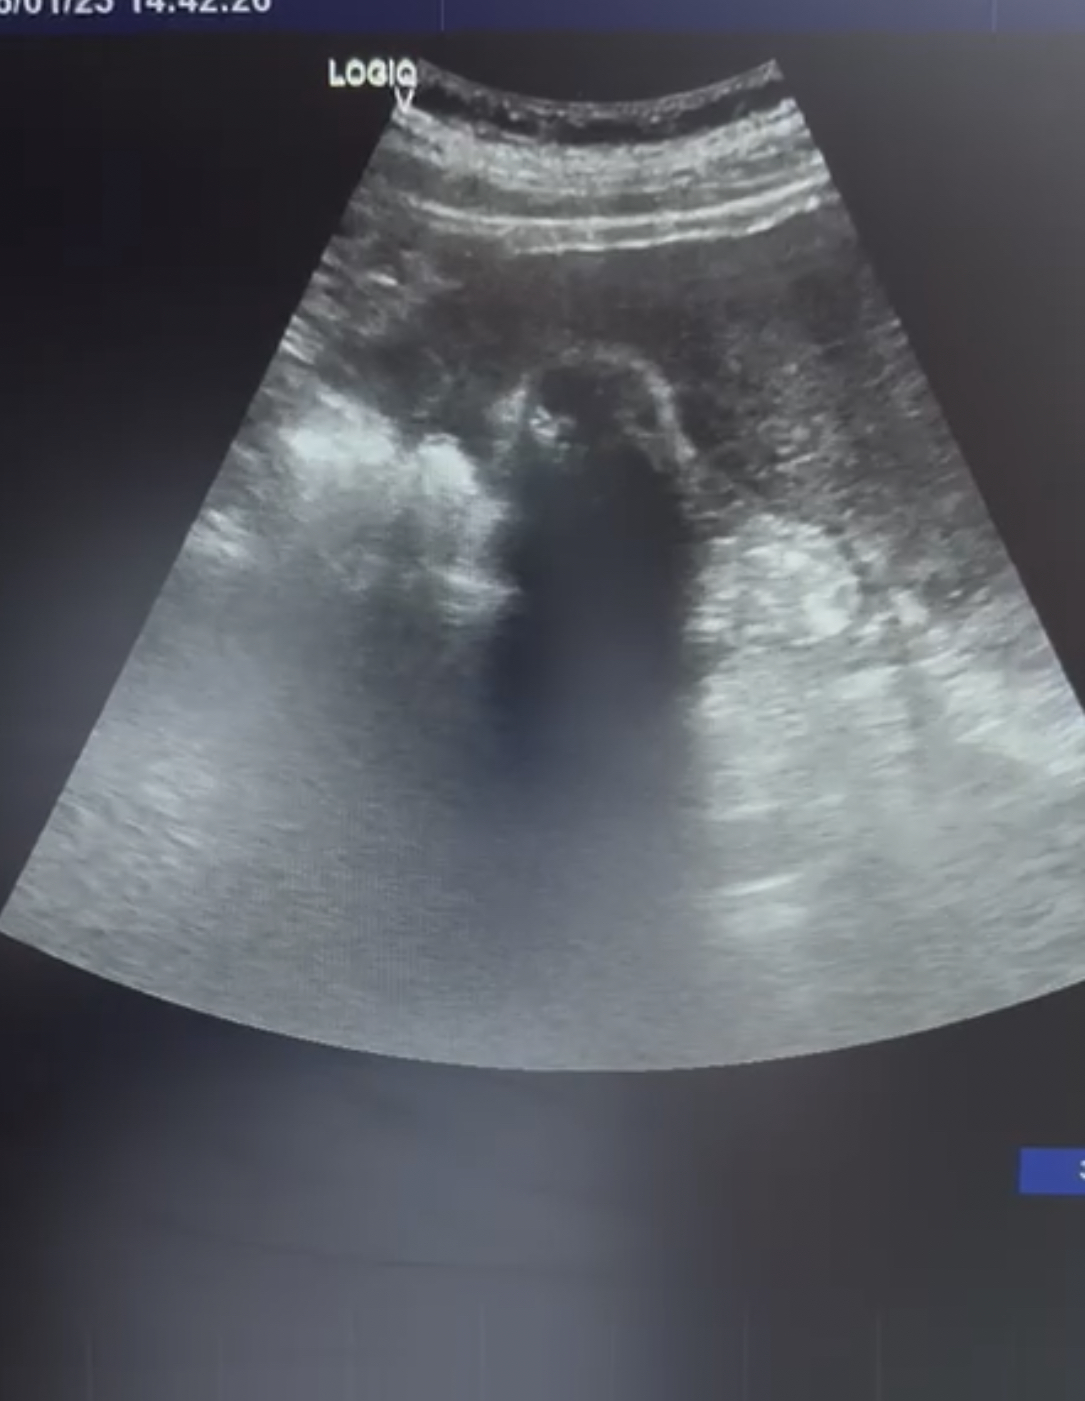

Se observa la vesícula biliar con varias litiasis en su interior y sombra acústica posterior. No se observan signos de colecistitis ni dilatacion de la vía biliar.